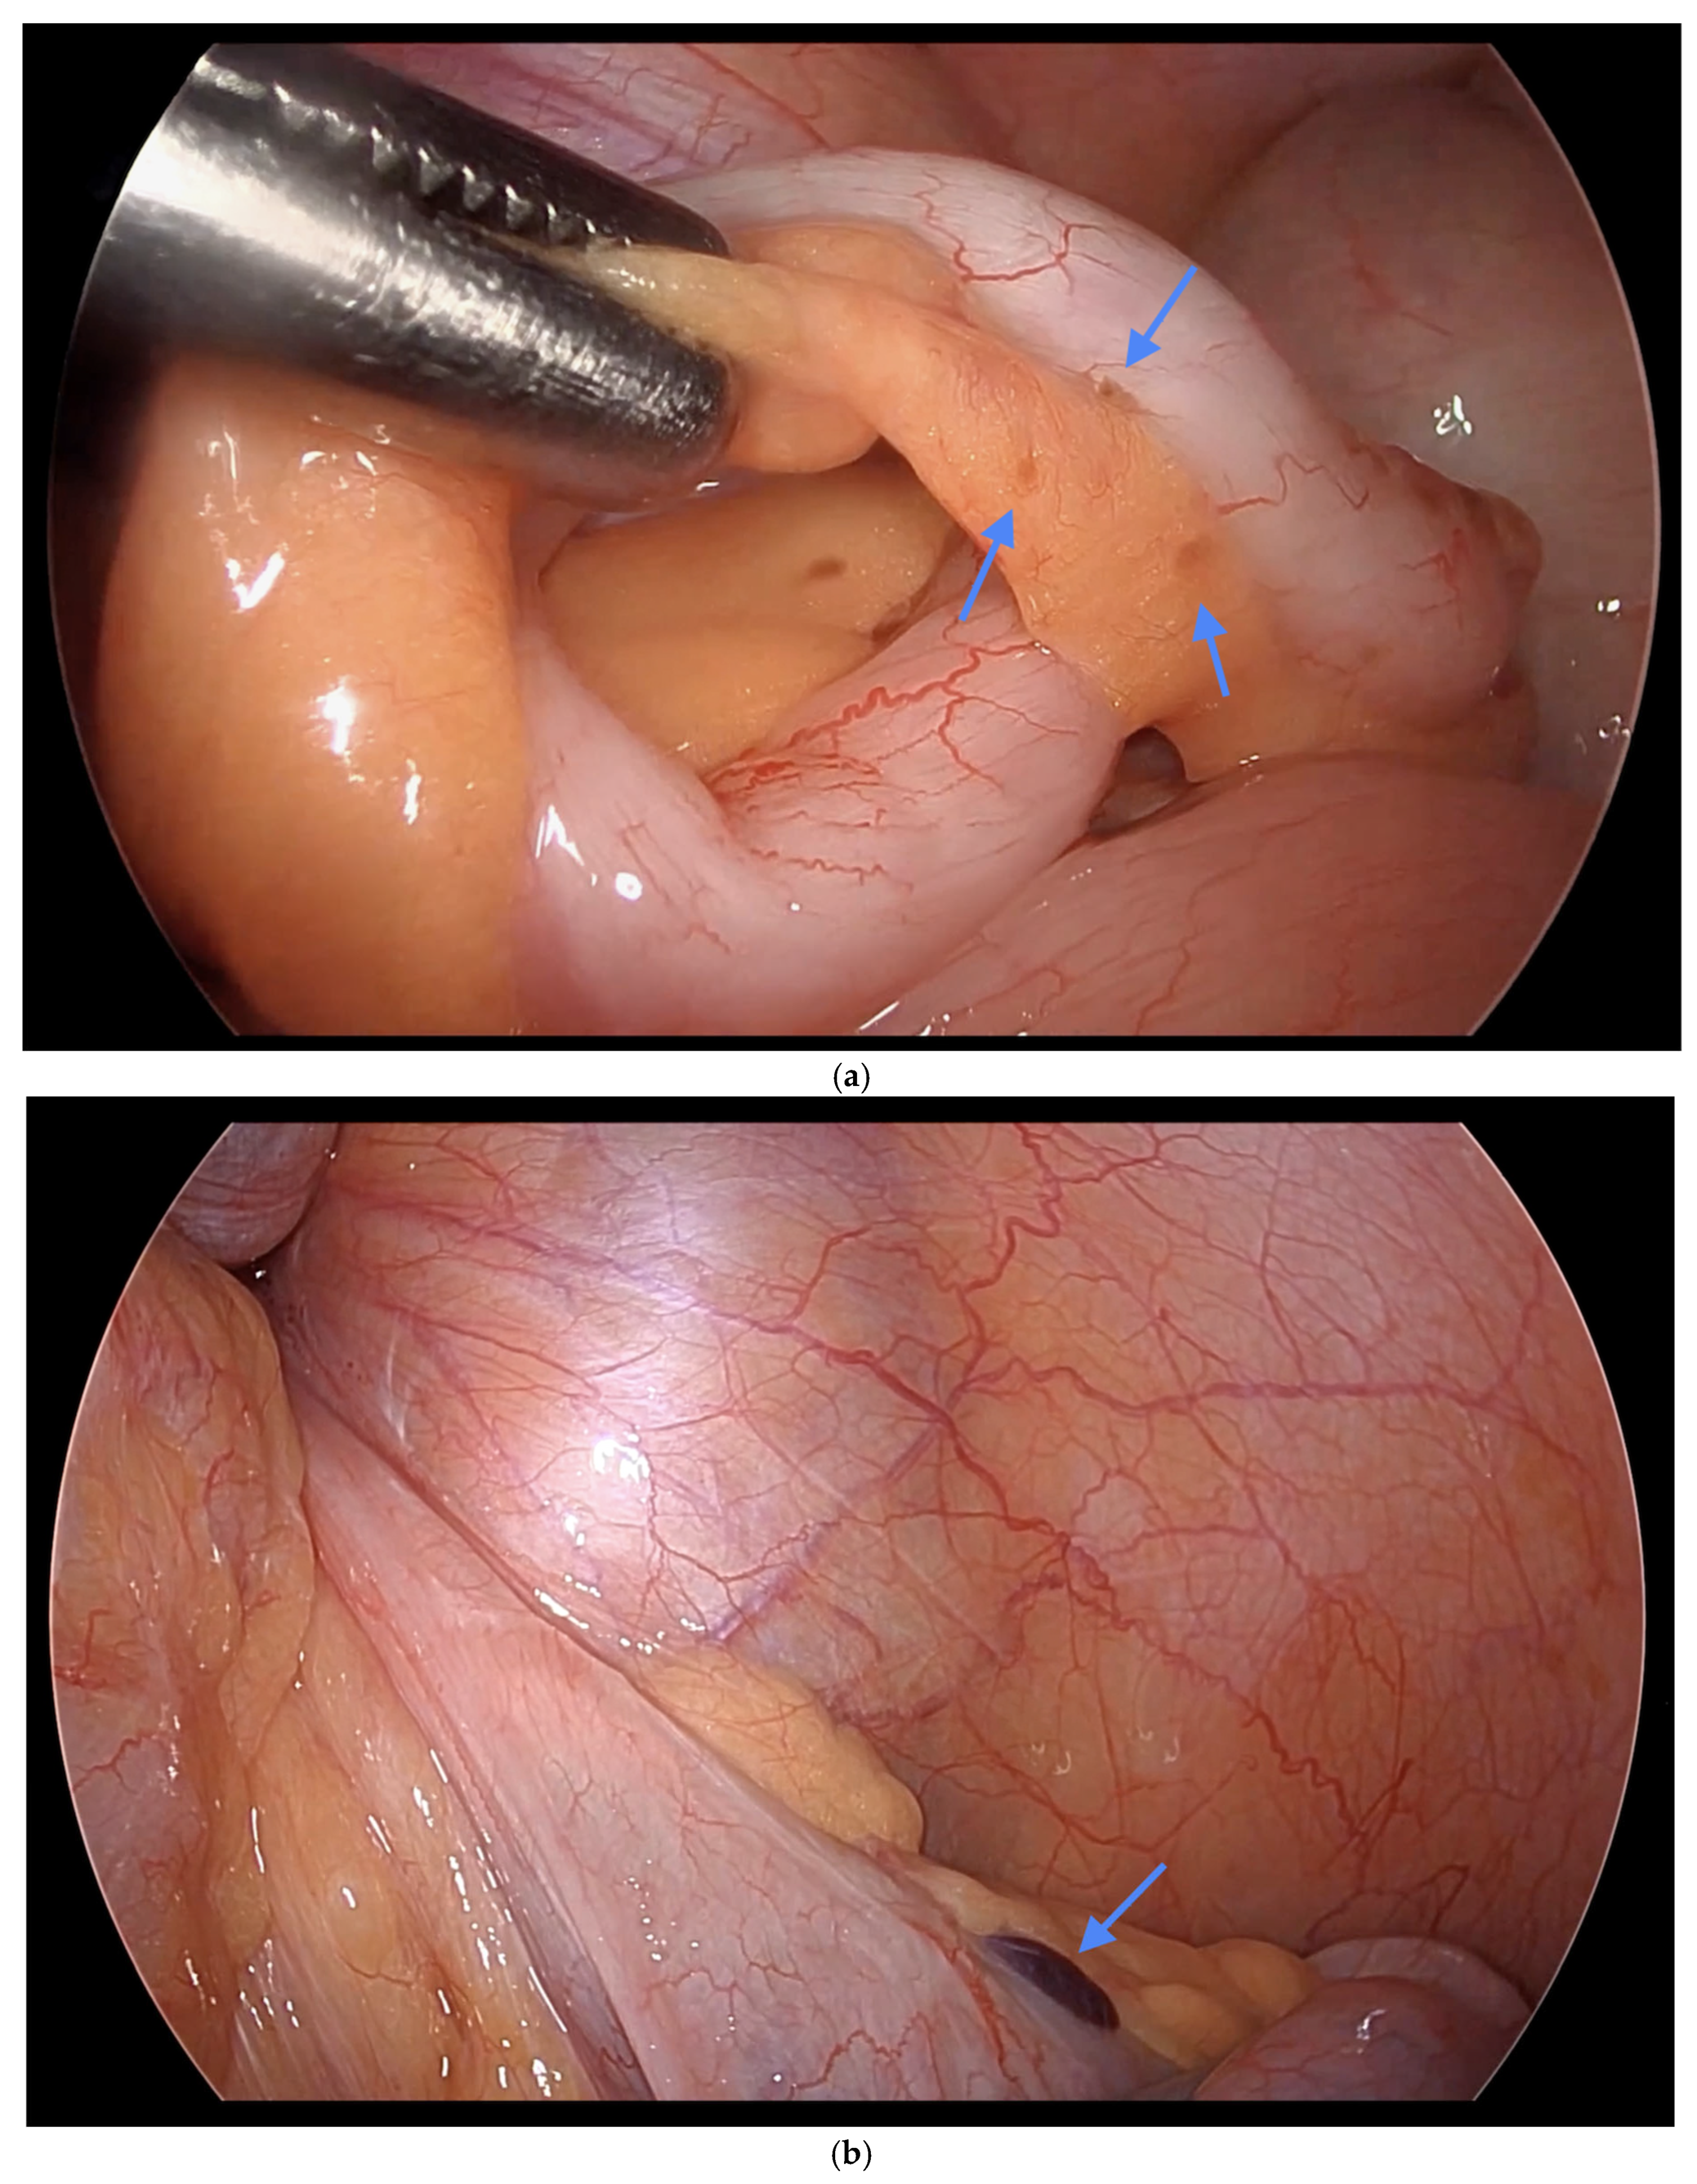

Figure 2. (a) i. Dense adhesions of the appendix to the uterus. ii. Endometriosis surrounding the peri appendix. (b) Vesicular lesions on the appendix. Blue arrows indicate (a) dense adhesions of the appendix to the uterus with endometriosis surrounding the peri-appendix, and (b) vesicular lesions on the appendix.

Informed consent was obtained preoperatively, which included a discussion of the possibility of intraoperative appendectomy if appendiceal abnormalities were identified. During surgery, after optimal excision and ablation of endometriotic lesions, the appendix was carefully evaluated for evidence of endometriotic implants, serosal abnormalities, adhesions, fibrous obliteration, or features suggestive of acute or chronic appendicitis (Figure 1, Figure 2 and Figure 3). If abnormal findings were present, intravenous metronidazole was administered for infection prophylaxis, and a laparoscopic appendectomy was performed using the existing port sites [15]. The surgical technique included division of the mesoappendix, followed by transection and closure of the appendiceal base using a vascular stapler. The specimen was placed into a laparoscopic retrieval pouch and sent for histopathologic analysis [15,16].

Among the 216 patients with confirmed appendiceal abnormalities, many presented with more than one pathological finding (Figure 1, Figure 2 and Figure 3). Specifically, 34 patients (14.41%) had histologically confirmed appendiceal endometriosis lesions, 140 patients (59.32%) showed focal or serosal adhesions, 82 (34.75%) demonstrated fibrous obliteration, typically observed as obliteration of the appendiceal tip, and 20 (8.47%) exhibited signs of inflammation. Notably, three cases were diagnosed with neuroendocrine tumors of the appendix: one was confirmed to be malignant, while the other two were benign (Table 2).